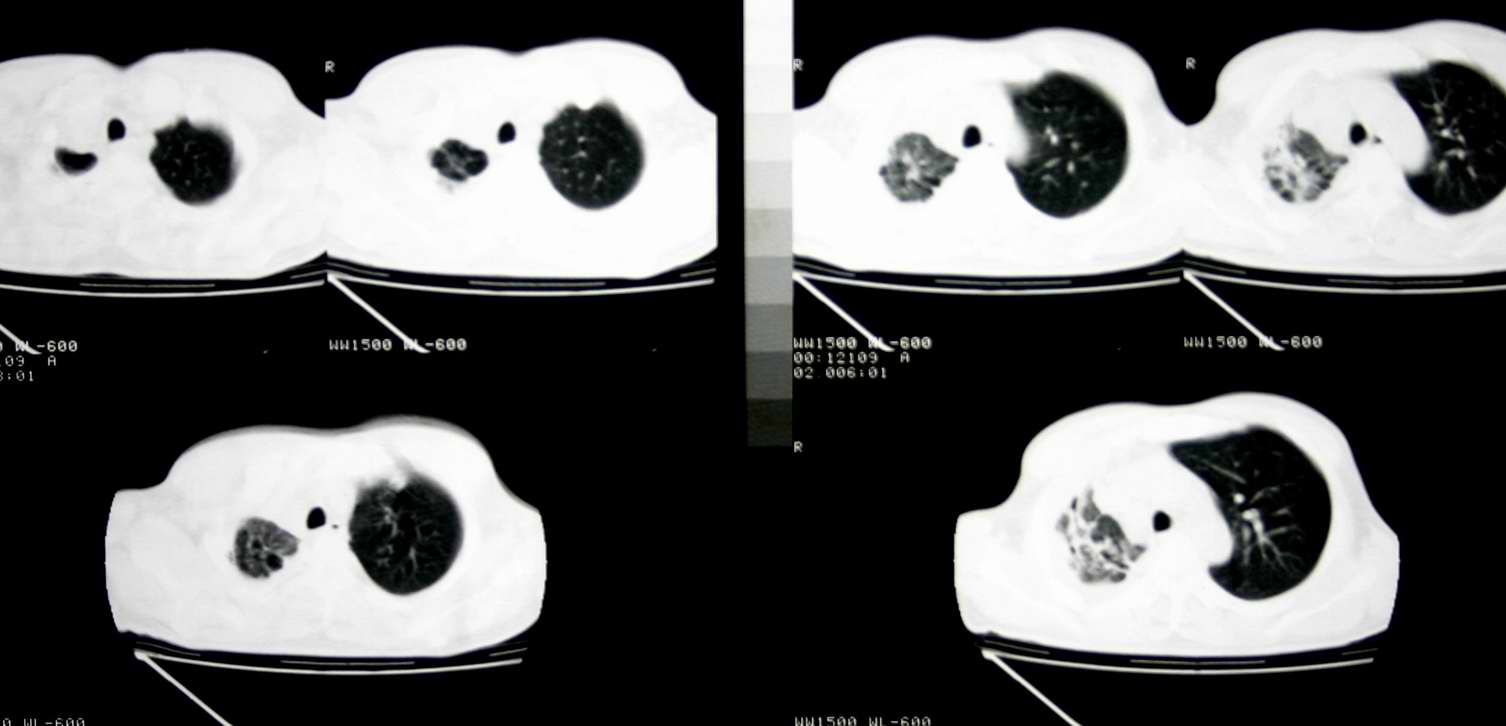

患者,男 ,48岁,反复咯血三个月,每三到五天咯一次,每次约200ml,鲜红色,无明显咳痰,咳嗽明显,无明显胸痛,无发烧,初期以抗感染、止血治疗,第一次ct报占位,支气管镜未见明显ca细,肺ca标志物、tb抗体均阴性,经过垂体后叶素、酚妥拉明、头胞他定、洛美沙星、立止血等治疗后,现病人一般情况好,停止咯血10天,咳嗽减少,咳黄脓痰,每日一次,每次30ml。现复查ct

右肺膨胀不全,纵隔右侧移位。肺内有感染,胸腔有积液。建议老片对比。

1)考虑右肺继发性肺结核合并感染。2)右侧胸腔积液+胸膜增厚。